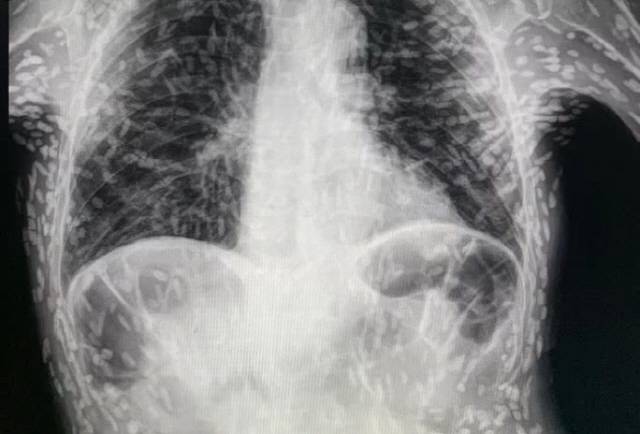

지속적인 기침과 복통으로 병원을 찾은 한 브라질 환자의 몸속에서 수백 마리의 기생충이 발견됐다.

최근 영국 일간지 데일리메일은 브라질의 한 의사가 자신의 소셜 미디어에 수백 개의 점 형상을 이루고 있는 엑스레이 사진과 관련된 소식을 보도했다.

유구낭미충증은 돼지고기나 소고기 등 육류를 제대로 익혀 먹지 않았을 때 사람의 몸속에 침투하는 유구조충의 유충인 유구낭미충에 의해 발현된다. 육류를 덜 익히면 기생충이 사람에게 들어와 소장에 기생한다. 기생충 알이 소장 벽을 뚫고 혈액으로 침입, 뇌의 중추신경계까지 감염시킨다. 이로 인해 두통, 복통, 심한 기침, 발작, 시력 저하 등 문제를 일으킨다.

세계보건기구(WHO)는 유충 낭종으로 인해 뇌에 생기는 낭종이 뇌전증 유발의 주원인이 된다고 설명한다. 매년 250만명이 유구조충에 감염되고 있으며, 대부분의 경우가 아시아, 남미, 동유럽 지역에 몰려 있다.

한편 해당 사진을 공개한 의료진은 해당 환자가 특별한 치료를 받지는 않았다고 밝혔다. 의료진은 “머리, 척수, 눈에 이상이 생긴 것이 아니라면 치료를 받을 필요가 없다”며 “해당 물체들은 석회화되었기 때문에 생존 가능한 유충이 아니다. 불편함을 느끼지만 않는다면, 특별한 조치가 필요하지는 않다”고 밝혔다. 다만 남아있는 낭종이 뇌나 눈에서 발생할 경우 문제가 될 수 있으므로, 환자는 뇌의 낭종 위치를 확인하기 위해 MRI 검사를 기다리고 있다.